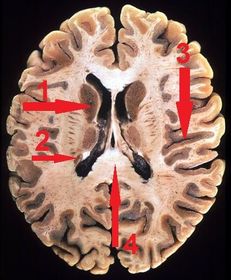

1) identify 1,2,3,4 1) head of caudate 2) tail of caudate 3) insula 4) splenium of corpus callosum